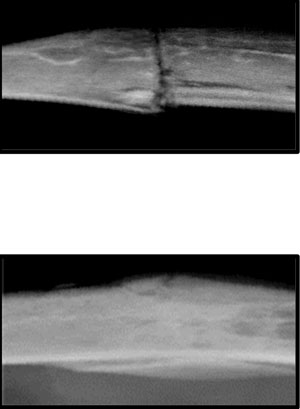

The research team not only traced what signals go wrong when older bones don’t heal properly, but also successfully manipulated the process in mouse models by both circulating blood and transplanting bone marrow from a young mouse into an older mouse. This prompted the older mouse’s bones to heal faster and better, more like the bones in the younger mouse.

In the new study, the researchers found that they could manipulate beta-catenin levels by exposing older mice to the blood circulation of younger mice, essentially correcting the intricate formula necessary for the healthy bone repair observed in younger mice.

The researchers replicated the findings using bone marrow cell transplantation from young to old mice, again demonstrating that young blood cells are able to recalibrate the beta-catenin signalling during early fracture repair, restoring healthy bone-healing in old mice.